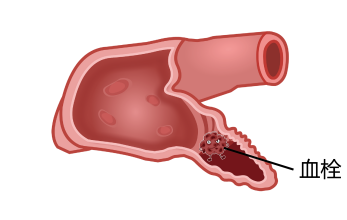

左心耳封堵是一种微创手术,手术时在心房颤动患者大腿根部血管穿刺并插入导管,进入心脏后精确定位,在左心耳入口处释放一个外表覆有膜的草莓形封堵器,封堵住左心耳,从而消除了左心耳形成血栓的隐患,达到预防脑卒中的目的(图3)。

图3.心耳造影左心耳封堵器外形与心耳对应关系